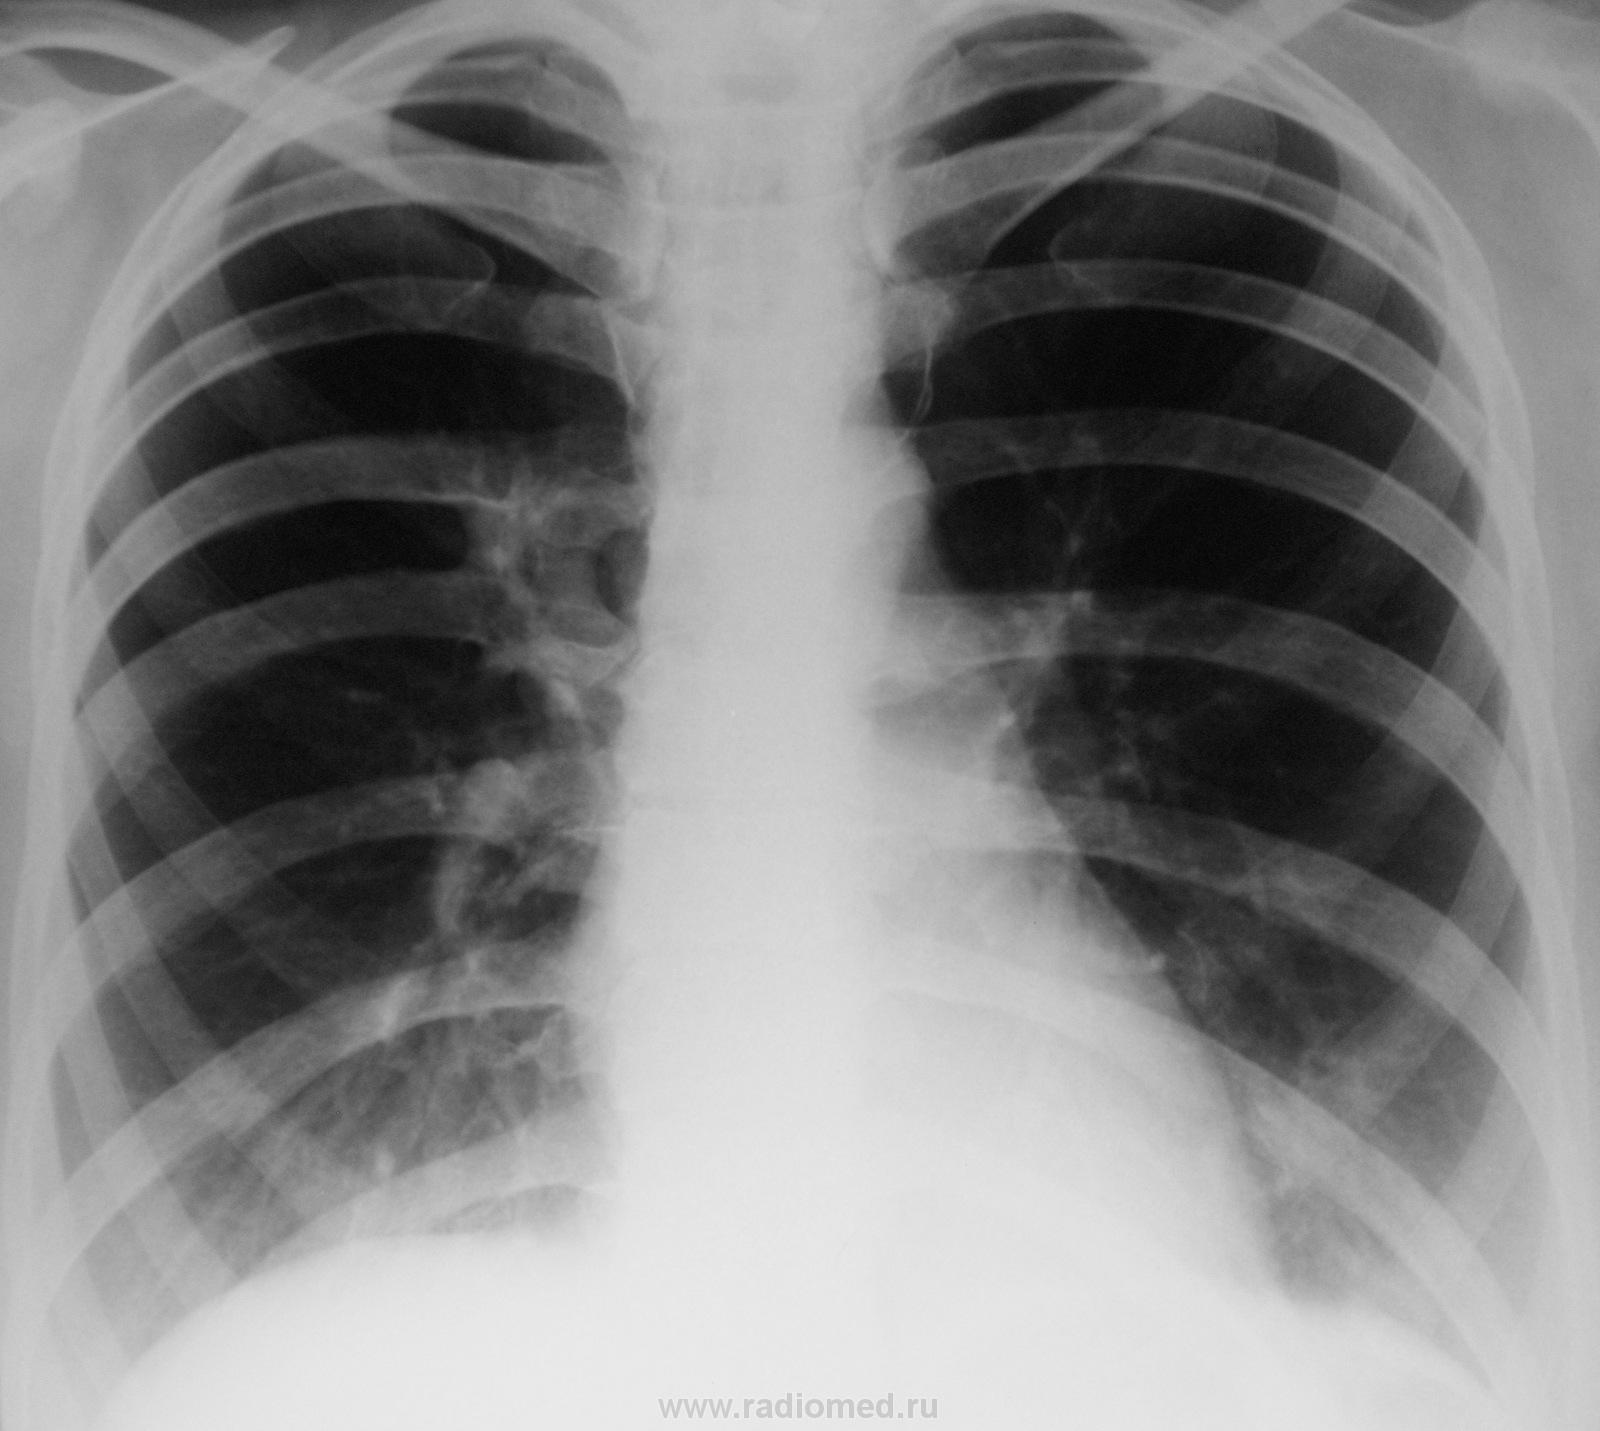

Медицина и диагностика: Аномалии ребер на рентгене